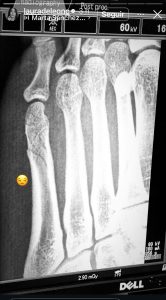

Recientemente, por medio de una publicación en Instagram, la actriz confesó que había sufrido un accidente que terminó causándole una “fractura oblicua”, una lesión que ocurre cuando el hueso se quiebra en diagonal, generando un dolor intenso y una recuperación más lenta. Según contó, lleva cuatro días soportando las molestias, pero que aún le faltan 30 días así.

“Esta es mi primera fractura en su vida, no quiero volver a fracturarme, gracias a Dios, no es peor, no es de cirugía (…)gracias por todos los consejos, que la bolsa para bañarse, que la almohadilla o los flotadores“, mencionó la actriz.